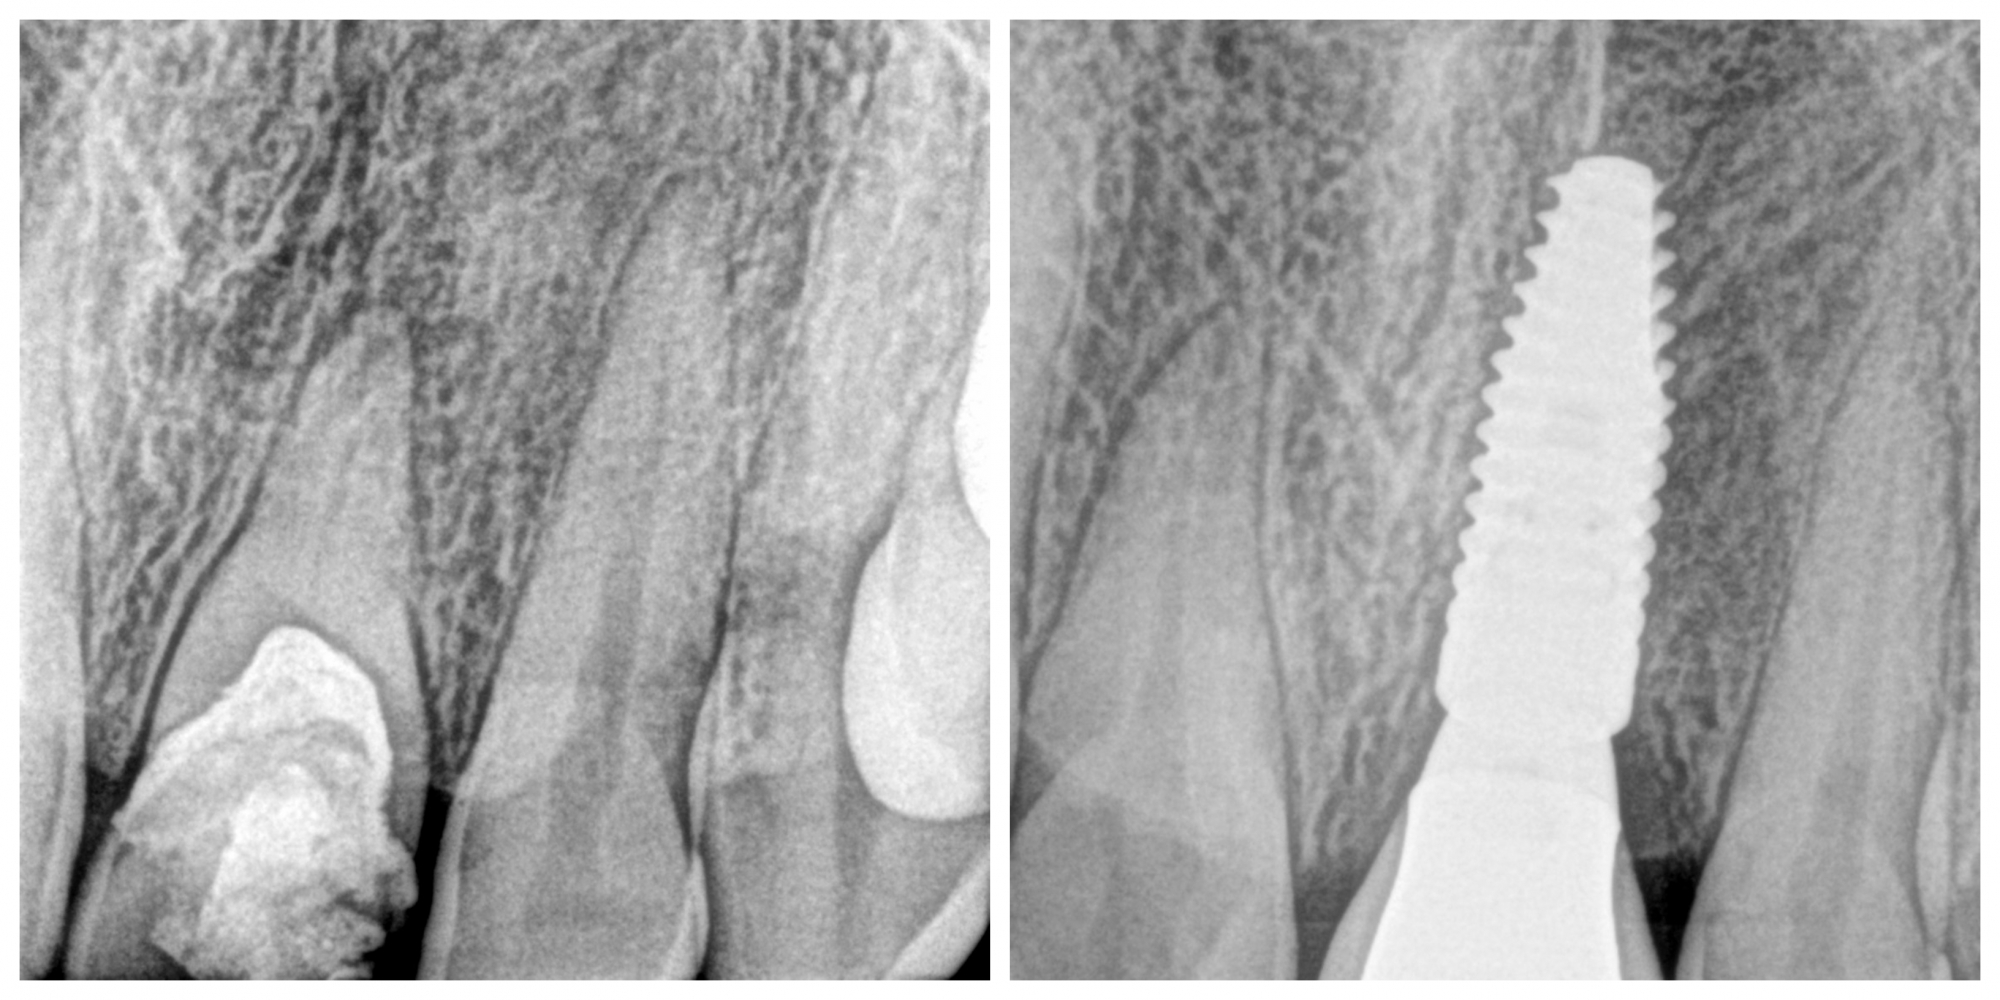

• Neatjaunojama zoba atraumatiska ekstrakcija (izraušana)

• Tūlītēja zoba implanta ievietošana un pagaidu kronīša (plastmasa) izgatavošana.

• Pēc 5 mēnešiem tika izgatavots slāņots cirkonijkeramikas kronis